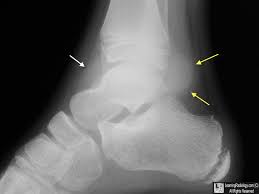

ankle effusion

build up of fluid in ankle joint

bone spurs

calcium deposist found commo